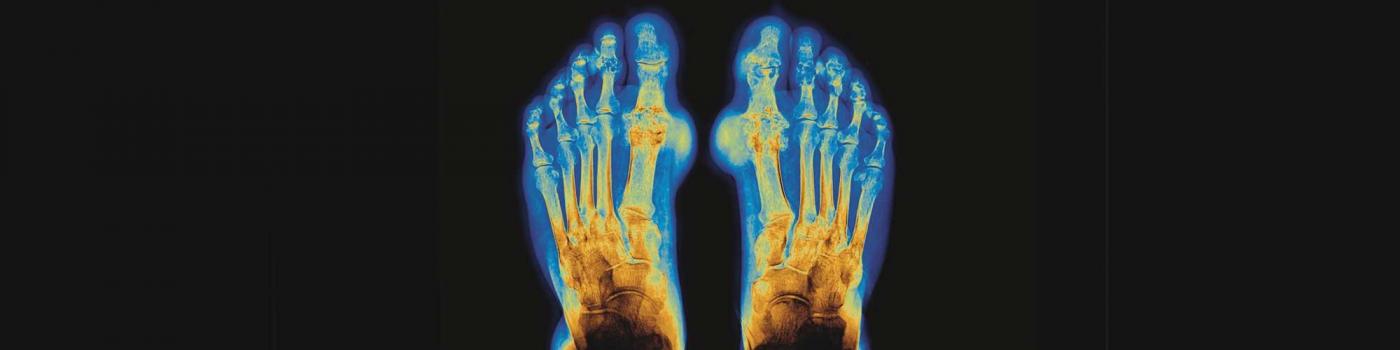

Faux. Maladie inflammatoire, la goutte se caractérise par des épisodes soudains de douleur sévère, le plus souvent au niveau des articulations. Elle affecte généralement d’abord le gros orteil, mais peut toucher toutes les articulations et même la peau à un stade avancé.